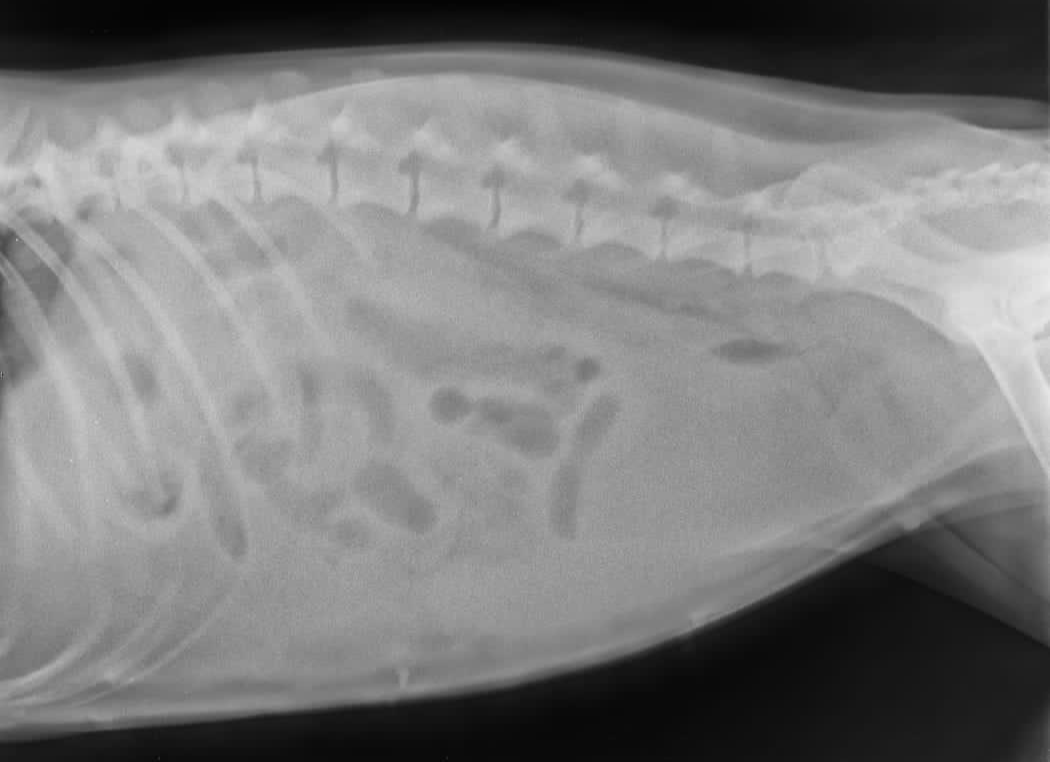

later xray after 2 days showing free fluid filling the abdomen